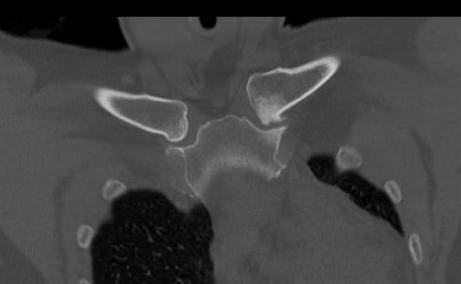

SCJ OA on the left with osteophytes and joint narrowing

Incidence

- 460 CT scans of SCJ

- 53% signs of asymptomatic OA

- 90% > 50 years old

- 100% > 60 years old